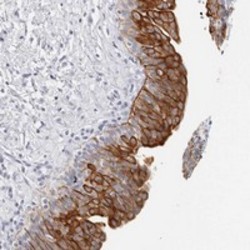

Supportive validation

- Submitted by

- Abnova Corporation (provider)

- Main image

- Experimental details

- Immunohistochemical staining of human urinary bladder with RPH3AL polyclonal antibody (Cat # PAB21678) shows strong cytoplasmic positivity in urothelial cells at 1:200-1:500 dilution.

- Validation comment

- Immunohistochemistry (Formalin/PFA-fixed paraffin-embedded sections)